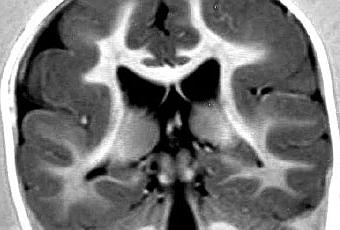

La superficie de un cerebro normal está formada por una serie compleja de pliegues y surcos. Los pliegues se denominan giros o circunvoluciones y los canales se denominan surcos. En niños que padecen de lisencefalia, las circunvoluciones normales están ausentes o se han formado solamente en parte, haciendo que la superficie del cerebro sea lisa. Los niños afectados suelen mostrar retraso psicomotor grave, retraso del desarrollo, convulsiones y espasticidad muscular o hipotonía.